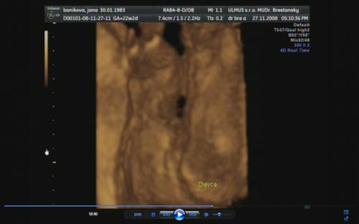

30.10.2008 - výsledky skríningových testov dopadli na jednotku, veľmi sa tešíme a dňa *****27.11.2008 - sme sa objednali na 3D ultrazvuk, tak som zvedavá, či nám potvrdia dievčatko a uvidím to na vlastné oči ... všetkým sa akosi zdá, že to bude chlapec 🙂 ....

Tak a máme to za sebou, náš 3D ultrazvuk, na ktorý sme sa moc moc tešili, bolo to úžasné, naša bambula Simonka sa nám ukázala v plnej kráse, akurát si zakrývala tváričku a nie a nie sa nám ukázať ... ale pár fotiek sa predsa len podarilo..pán doktor všetko prezrel a zatiaľ sa všetko vyvíja tak ako má .....